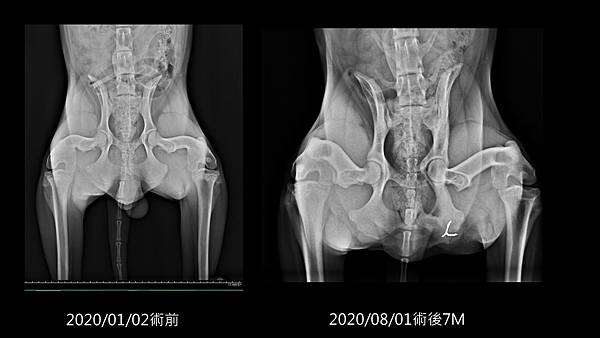

前天晚上在縫補被周周咬的破破的熊,半夜11點時突然發現擱置在桌上的縫針消失了,地上也都找不到,當下就懷疑是不是被周周吃了,但彰化的動物醫院都關門了,周周也沒有任何不舒服的症狀,照吃照睡照拉照玩照追貓咪,只好先密切觀察看看。

不囉嗦,先上圖(因為英國皇家動物醫院說有骨板的X光片牽涉醫師的智慧財產權,所以只能copy沒骨板的X光片):